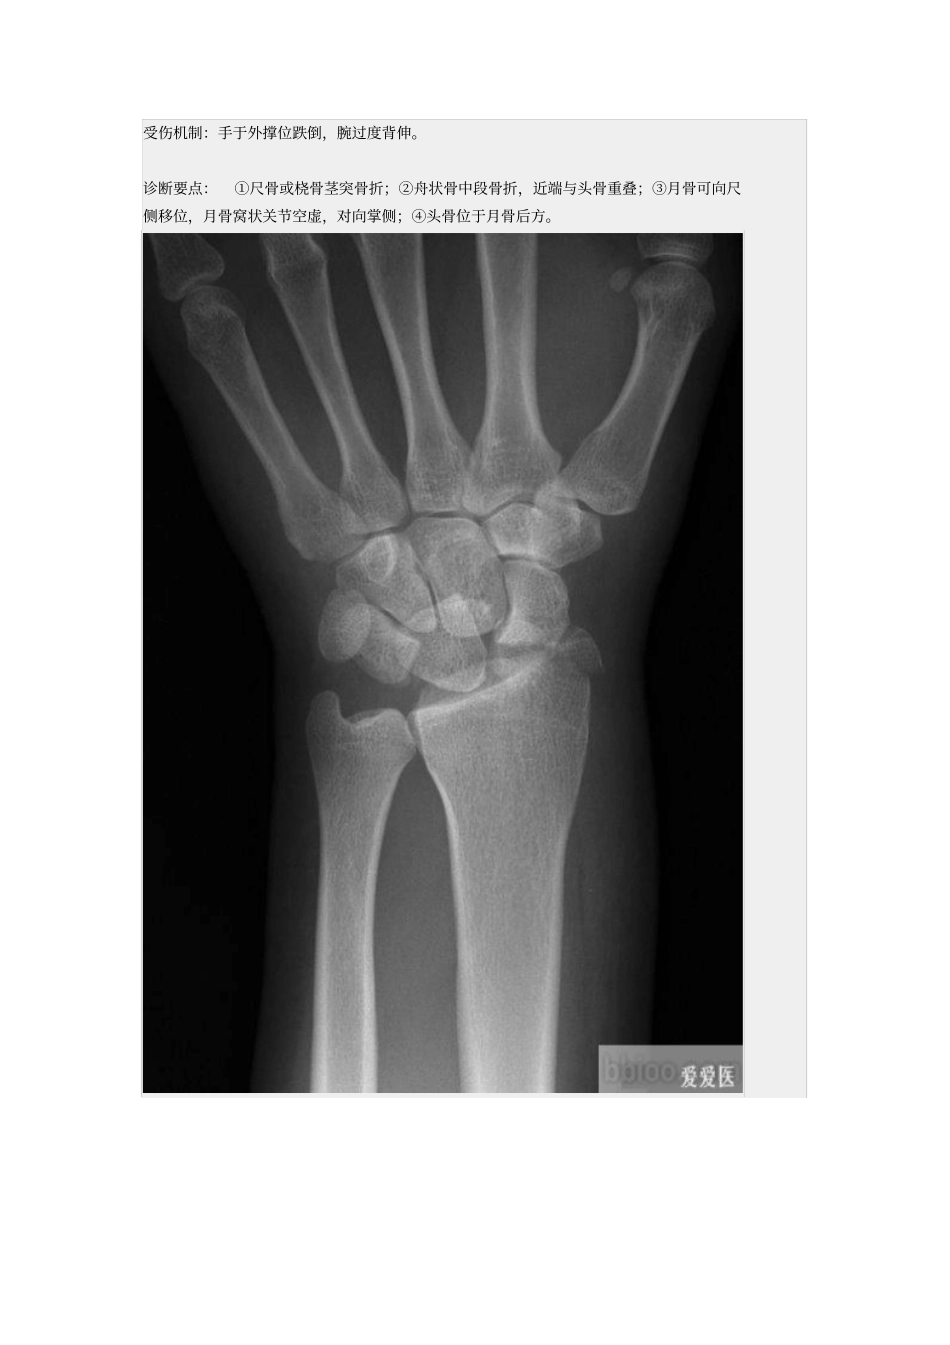

一、月骨脱位受伤机制:手于外撑位跌倒。诊断要点:①正位片月上骨旋转与头骨重叠,头月关节、桡月关节间隙可消失;②侧位片上月骨向掌侧脱位为特征性表现;③舟状骨、头骨与桡骨关系保持原位不变。二、经茎突和舟状骨的月骨脱位受伤机制:手于外撑位跌倒,腕过度背伸。诊断要点:①尺骨或桡骨茎突骨折;②舟状骨中段骨折,近端与头骨重叠;③月骨可向尺侧移位,月骨窝状关节空虚,对向掌侧;④头骨位于月骨后方。三、月骨周围脱位受伤机制:摔倒时手背伸、尺偏和旋前位着地,发生月骨周围脱位。临床表现:腕部肿胀向背侧突出,屈伸活动受限,局部疼痛、压痛。诊断要点:①正位片上头月骨重叠,关节间隙出现消失或变窄;②侧位片上月骨原位不动,桡月关节正常, 月骨上关节面空虚;③头状骨位于月骨背侧缘的后上方;④舟状骨向背侧脱位;⑤可伴有桡骨背缘骨折。四、经舟状骨月骨周围脱位受伤机制:摔倒时手背伸、尺偏和旋前位着地,发生月骨周围脱位。诊断要点:①舟状骨骨折;②正位片上头月关节间隙异常;③侧位片上月骨原位不动,舟状骨近侧骨折块和月骨与桡骨的关系正常,月骨上关节面空虚;④头状骨位于月骨背侧缘的后上方。五、经茎突和舟状骨的月骨周围脱位受伤机制:跌倒时手掌着地,腕过度背伸。诊断要点:①尺、桡骨茎突骨折;②舟状骨中段骨折,近端与头骨重叠;③月骨可向尺侧移位,月骨窝状关节空虚;④头骨位于月骨后方;⑤月骨和舟状骨近端与桡骨关节可正常或向掌侧半脱位。六、三角骨月骨周围脱位受伤机制: 本病的主要表现与月骨周围脱位相似,只是三角骨与钩骨关节间的脱位取代了三角骨与月骨关节间脱位。诊断要点:①月骨、三角骨及桡骨三者关系正常;②其余腕骨向背侧脱位。七、舟状骨脱位受伤机制:舟状骨有旋转性半脱位与全脱位两种类型,两者受伤机制完全不同。前者系中腕关节移位时致舟状骨近端发生旋转性半脱位,较常见;而舟状骨全脱位为直接暴力所致,非常罕见。诊断要点:腕部症状多较严重,有时可伴有神经受压症状。脱出的舟状骨位于皮下,可触及。八、小多角骨脱位受伤机制: 小多角骨脱位较罕见,可为单独脱位,或合并邻近骨的骨折或脱位,脱位的小多角骨多脱向背侧。